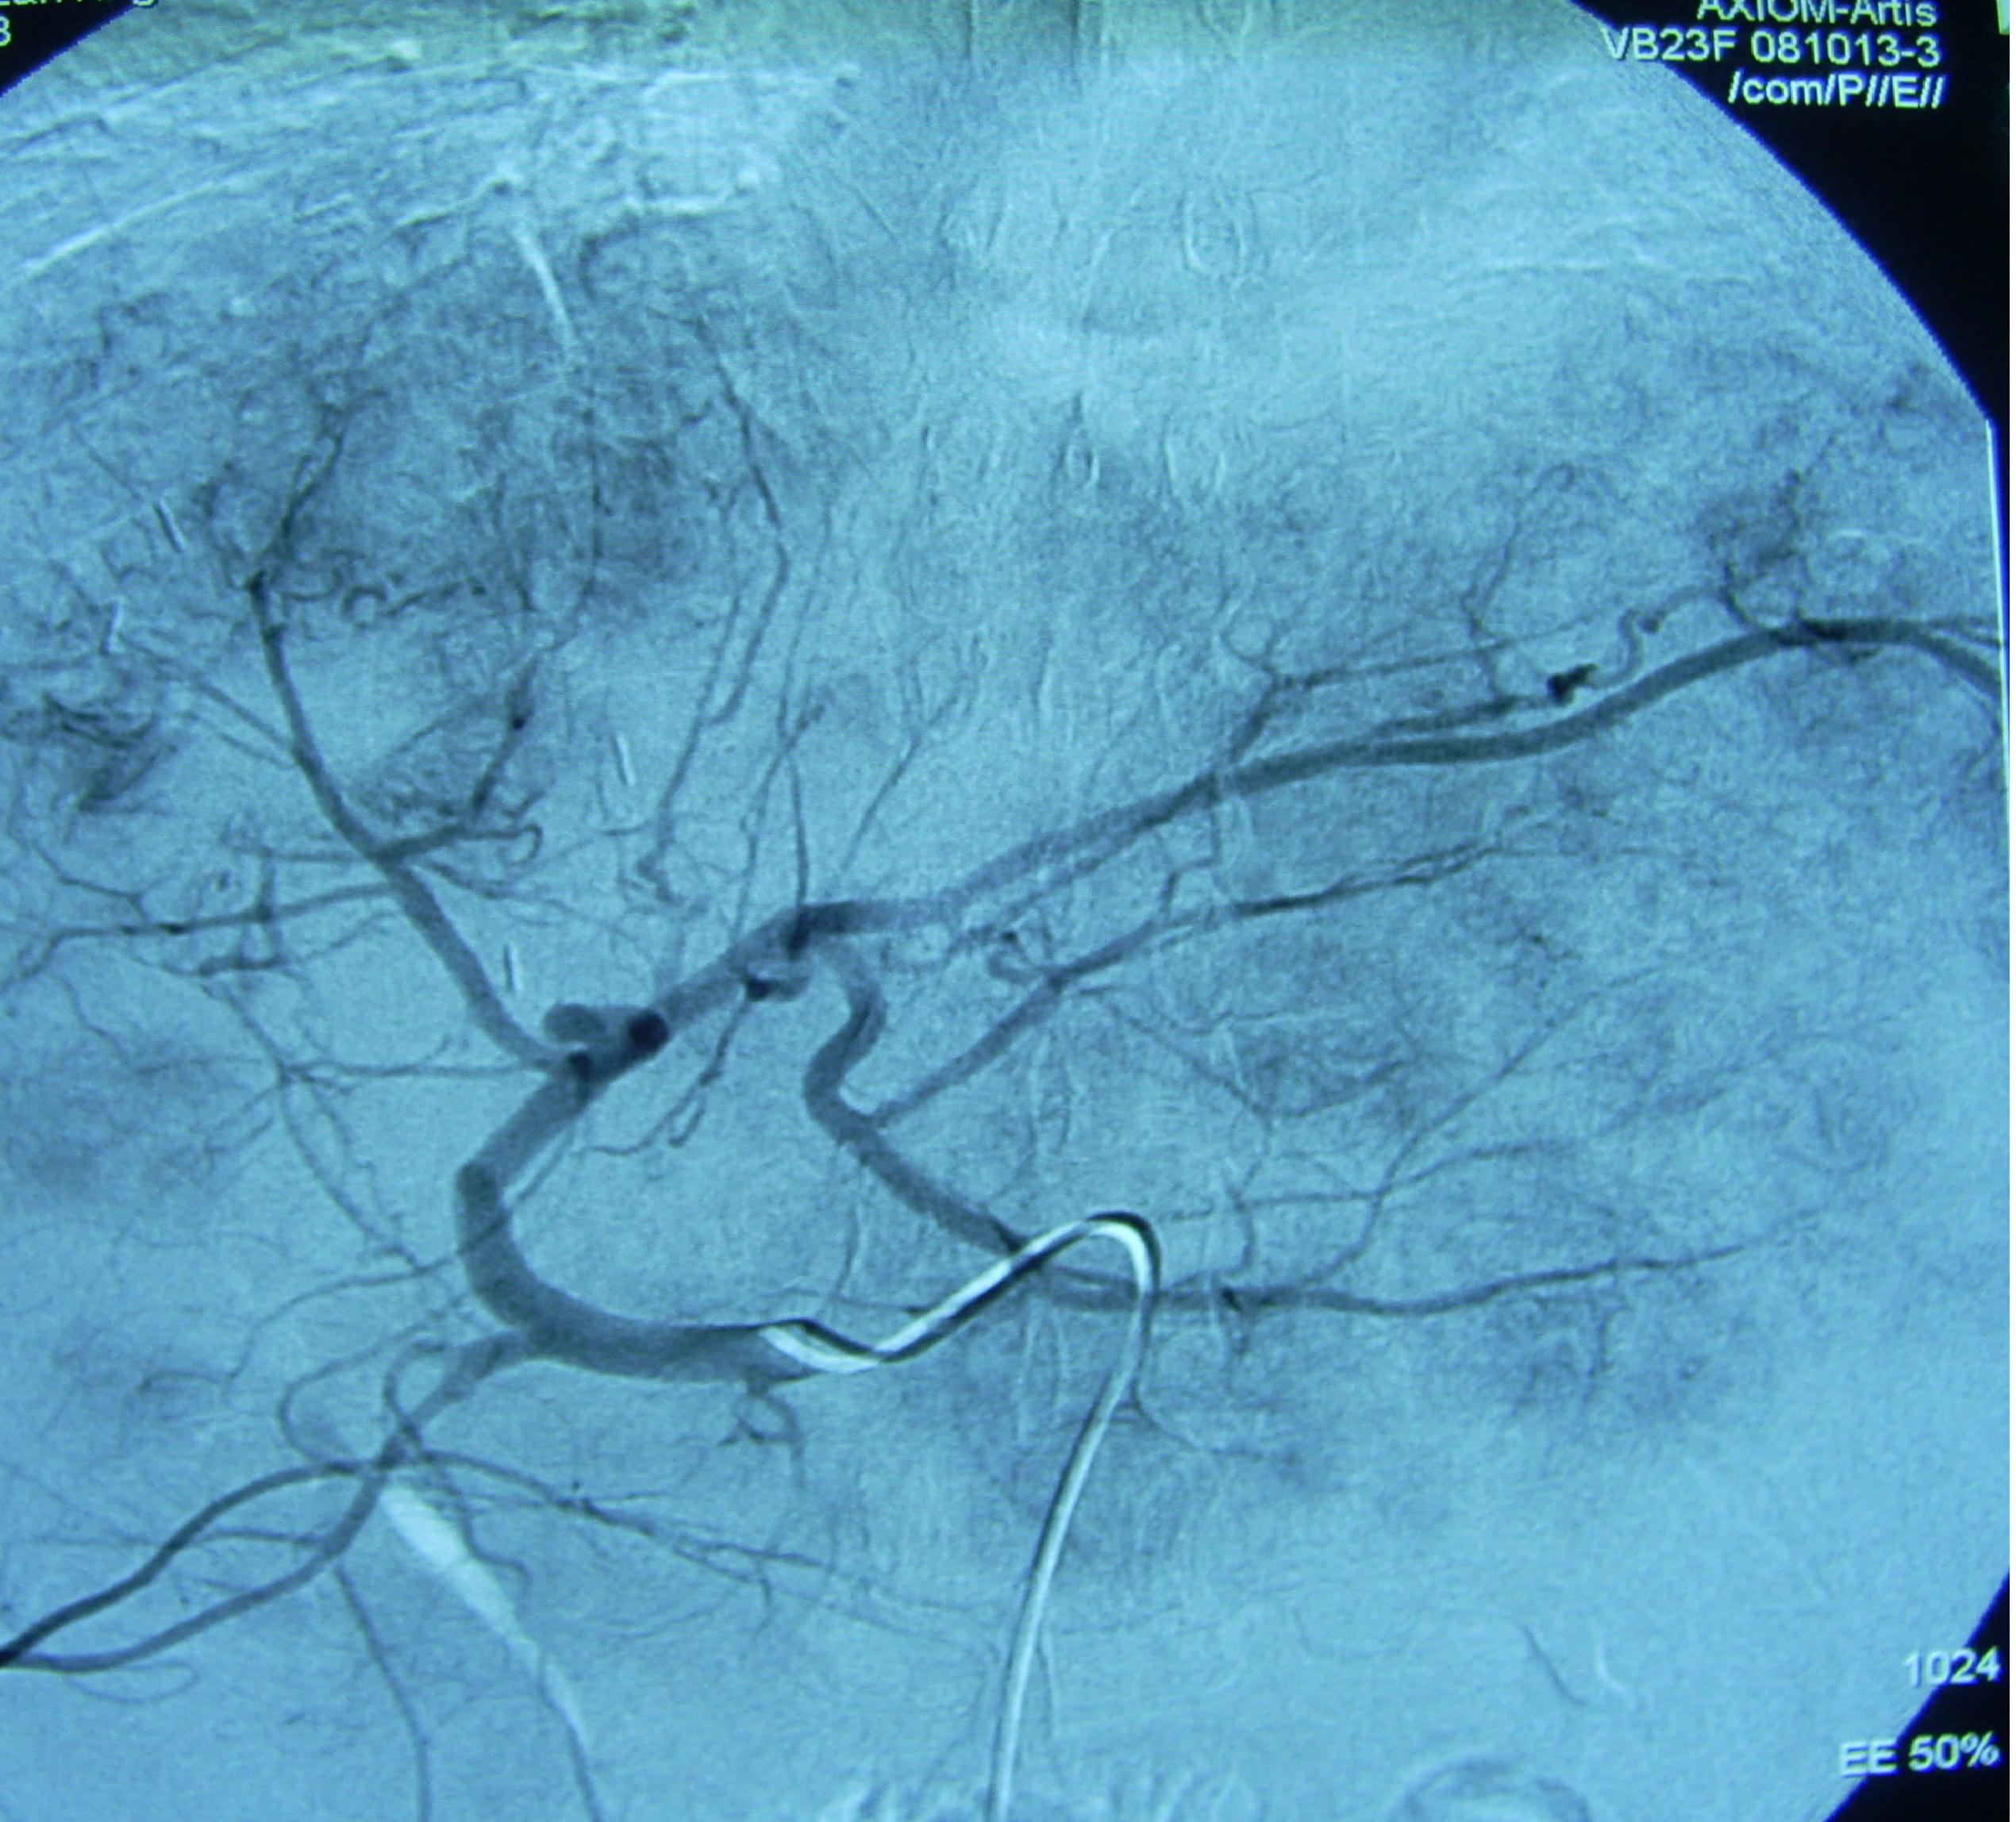

血管造影显示肿瘤组织在肝内弥漫分布

治疗过程:确诊后第2天进行经导管动脉化学栓塞治疗,也叫微创介入治疗。化学药物配伍方案为氟尿嘧啶脱氧核苷和羟基喜树碱,栓塞材料为无水乙醇和碘化油混悬液。治疗后2小时有恶心,无呕吐,肝区胀痛,给予颅痛定120毫克肌肉注射,15分钟后入睡。第2天早晨6点体温38.2摄氏度,采用物理降温,20小时后温度恢复正常。治疗后第4天出院,回家口服芦笋精胶囊,每天3次每次2粒,谷胱甘肽每天3次每次400毫克。1月后复查,肝内肿瘤范围明显减小,肿瘤组织里面由明显碘化油沉积。患者行动自如,KPS评分100分。3月后复查肿瘤范围进一步减小,按照原方案做了第2次微创介入治疗,以巩固疗效。患者酷爱吃火锅,虽然医生反复告诫其危险性,半年后的一天,患者独自一人去吃了一次,几小时后突然发生上消化道大出血,呕吐鲜血和血凝块1000多毫升,很快发生休克和昏迷,急诊抢救无效而死亡。